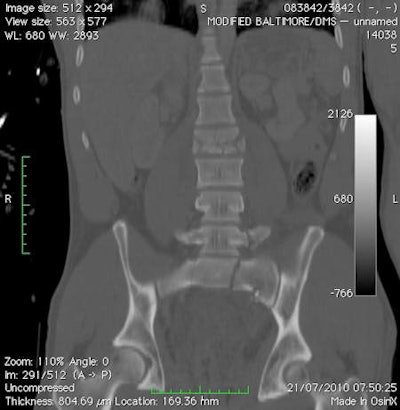

These two images are from a soldier in a vehicle hit by an improvized explosive device. Above: A lateral CT reformat of the cervical spine with an anterior inferior fracture of C5. Below: A coronal CT reformat of the sacrum and lumbar spine. The patient demonstrates a left vertical sacral fracture, left transverse fracture of L5, and burst fracture of L2. All images courtesy of Dr. Richard Graham.